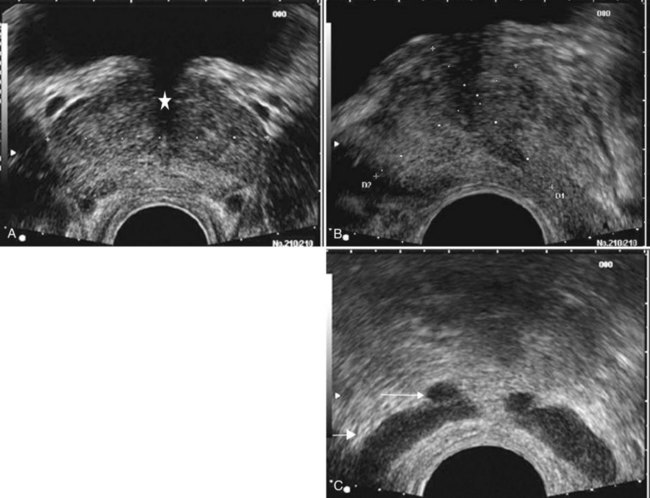

Figure 97–2 Classic gray-scale transrectal ultrasonography imaging of the prostate. A, In the transverse plane with the hypoechoic urethra centrally located (star) and dotted line representing transverse measurement. B, Midline sagittal view with the hypoechoic urethra running the length of the gland, D1 represents longitudinal and D2 anteroposterior measurement. C, Seminal vesicles (large arrow) and vasa deferentia (small arrow) in the transverse plane.

The paired seminal vesicles (SVs) are positioned posteriorly at the base of the prostate (Fig. 97–2C). They have a smooth, saccular appearance and should be symmetrical. The normal SV measures 4.5 to 5.5 cm in length and 2 cm in width. A cystic SV mass is presumptively benign, whereas a solid lesion has a small probability of being malignant, especially if the patient has a primary neoplasm elsewhere. Schistosomiasis should be considered when making a differential diagnosis in patients who live in areas where infestation is endemic with a solid SV mass (Al-Saeed et al, 2003). In the transverse plane, the vasa deferentia course just above their ipsilateral SV before diving caudally toward the prostate near the midline. Here they lie just medial to the tapering ipsilateral SV before the two structures fuse to form an ejaculatory duct. The ejaculatory ducts (occasionally seen as a hypoechoic structure) enter the gland posteriorly and empty into the urethra at the verumontanum (see Fig. 97–2C). Their course parallels that of the prostatic urethra distal to the verumontanum.